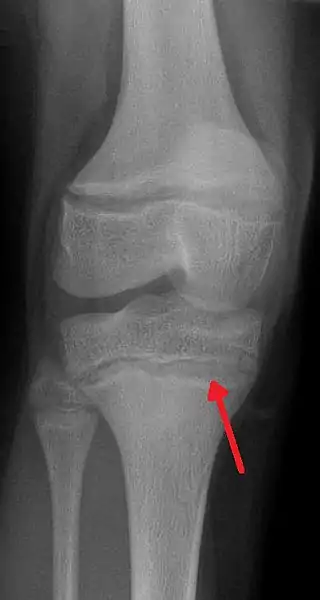

![]() Radiografía que muestra densas líneas metafisarias, características del saturnismo. | ||